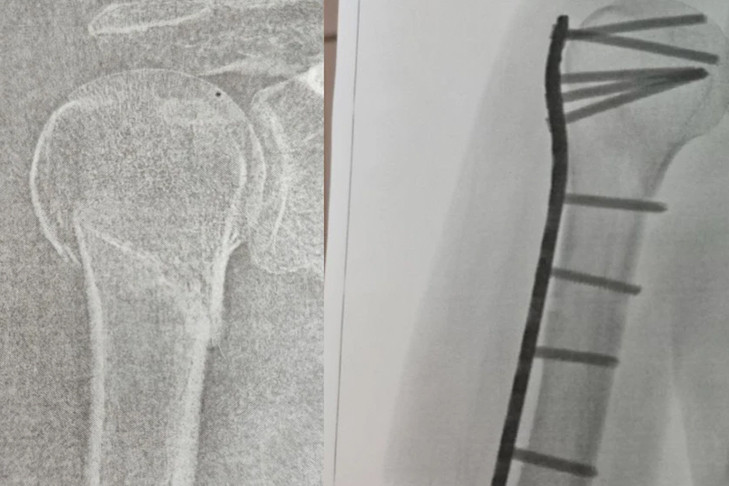

Муж Натальи вызвал скорую помощь. Медики забрали женщину, дали обезболивающее и наложили шину. В травмпункте рентген показал закрытый перелом плечевой кости со смещением отломков. Сибирячки пришлось проводить операцию — вставлять пластину и штифты.

«В марте выписали домой в гипсе. От слабости едва могла делать домашние дела, через 2 месяца гипс сняли. Правая рука висела «сама по себе», неподвижная, как будто после инсульта. Через боль я ее разрабатывала несколько месяцев», — продолжает женщина.

Через несколько месяцев Наталье удалось снять гипс, но рука безумно болела — пластина царапала кость. Металл пришлось доставать в частной клинике. В настоящее время женщина до сих пор проходит реабилитацию, а также пытается добиться компенсацию вреда от магазина.